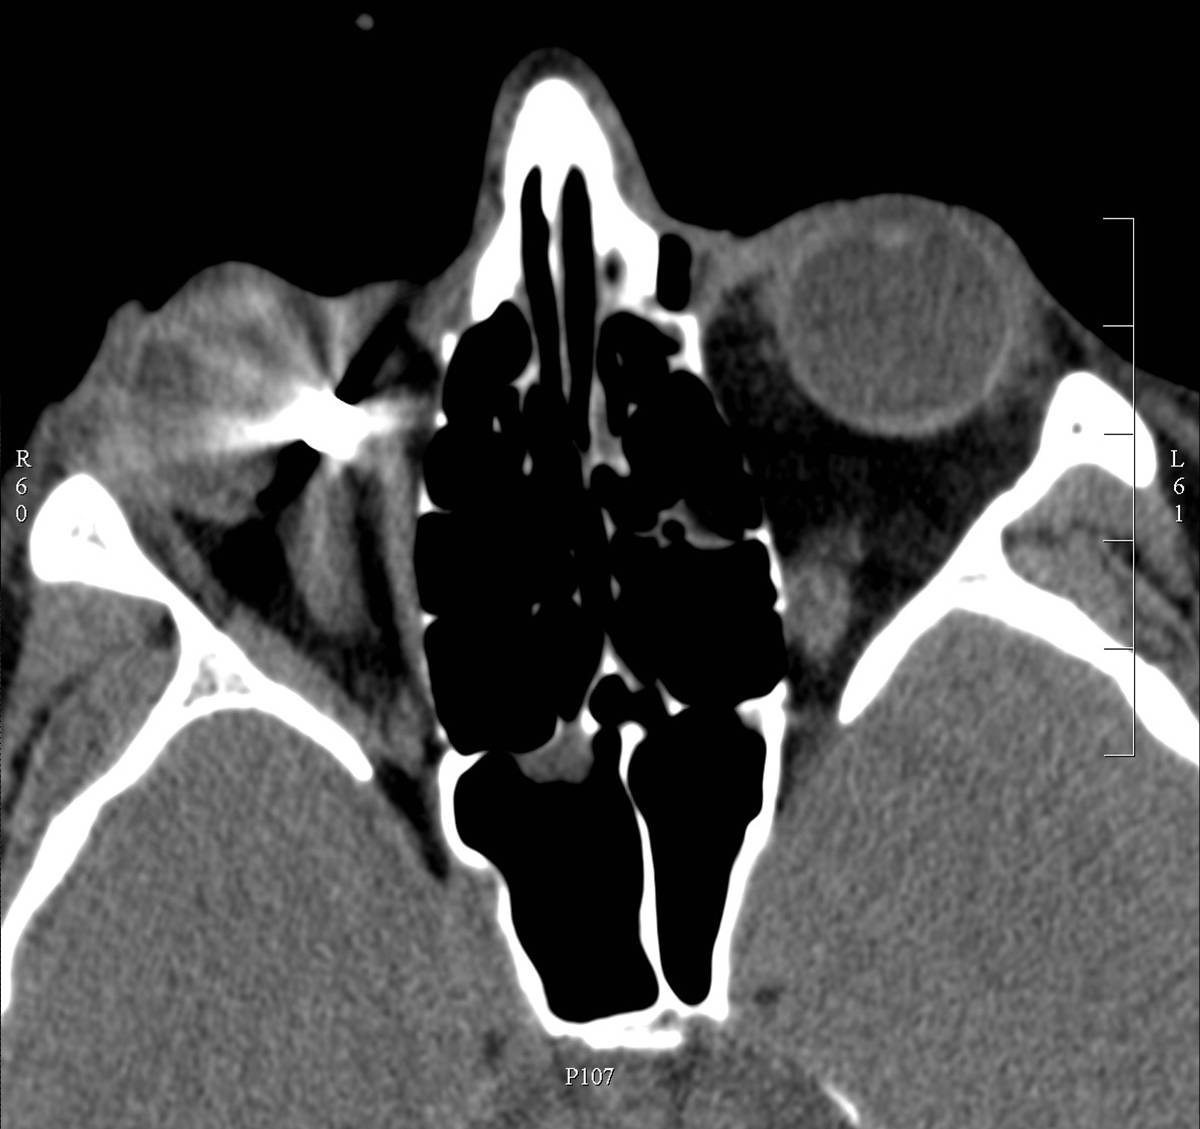

• Fractures of the skull base deserve special attention. The classification is based on their close proximity to the intracranial fossae. The fracture can expose the dura, and if the subarachonid space brakes open cerebrospinal fluid can appear outside of the skull. In case of an anterior fossa injury cerebrospinal fluid leaks through the nasal cavity, in middle-posterior fossa fractures it sips through the external auditory canal. When a fracture is suspected special attention should be given to the evaluation of air containing cavities (ie. nasal sinuses, tympanic cavity) on the base of skull.

• Among base of the skull fractures temporal bone, especially pyramidal fracture deserves specific mentioning. The reason for this the potential injury of the many important structures (organs of hearing, and balancing, the facial canal and segments of the internal jugular vein and carotid artery should be specifically mentioned) located in this bone. Due to the primarily bony structure CT is the mandatory method of choice (HRCT).

• Headache can caused by otological diseases as well, such as acute or chronic middle ear infection or inflammation of the mastoid cells. Imaging is necessary in recurrent or in acute fulminant diseases. Conventional x-ray studies (Schuller, Stenvers, Mayer view) are obsolete. Bony structures and air content should be evaluated with CT (high-resolution HRCT). MRI is performed in case of intracranial propagation and to detect complications.